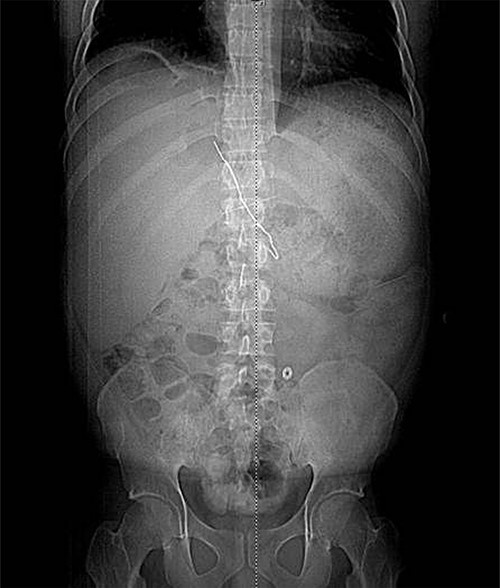

The patient underwent left hepatic abscess drainage and fluoroscopic-guided foreign body retrieval of intrahepatic foreign body. Through an image guided intercostal approach, an 0.035 inch guidewire was coiled within the hepatic abscess and a vascular sheath was introduced. The hepatic end of the paper clip was able to be snared, but could not be completely removed due to lack of traction. The snare was able to guide the end of the paperclip into the sheath where a high pressure non-compliant balloon (Conquest) was the inserted over an 0.035 inch stiff Glidewire and inflated in the sheath adjacent to end of the paperclip to wedge the paperclip into the vascular sheath, and under fluoroscopic guidance, the inflated Conquest balloon, paperclip and vascular sheath were successfully removed as a unit (Figs 4 and 5). A drain was left in the hepatic collection. The two small extraluminal foreign bodies were left in place.

Fluoroscopic image obtained intraoperatively demonstrating removal of the metallic foreign body